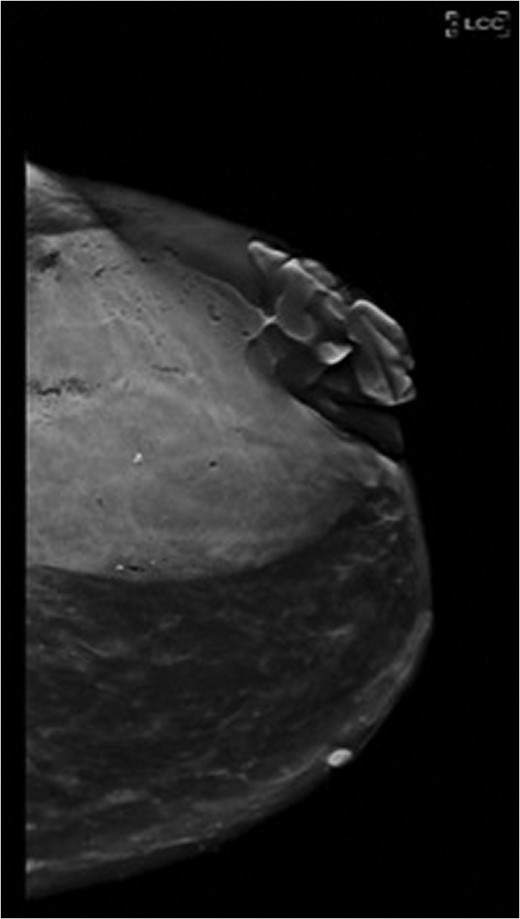

Physical exam revealed a large fungating mass extruding from the left breast at the 3 o'clock position with overlying ulceration and cellulitic changes to the surrounding skin (Fig. 1). CT scan of the chest demonstrated a 9.2 × 8.6 cm heterogeneous mass in the left breast with reactive lymphadenopathy up to 3.1 cm in the ipsilateral axilla (Fig. 2). There were no suspicious findings in the right breast on CT and mammographic imaging (Fig. 3). MRI of the brain demonstrated no evidence of metastatic disease. Core needle biopsy (CNB) of the mass demonstrated focal granulomatous reaction with foreign body giant cells. CNB of the enlarged axillary node was benign.

Craniocaudal view of the left breast on mammography demonstrates the extent of the fungating mass.